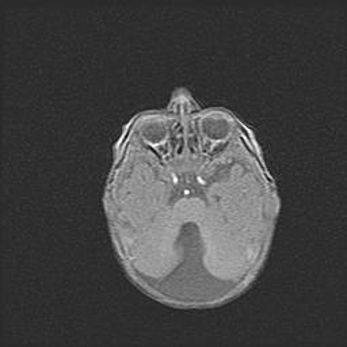

Церебральная ишемия II.

Возраст: 5 дней

Вес: 3400 г

Пол: женский

Окружность головы: 35 см

Срок гестации: 39 недель

Церебральная ишемия – это заболевание, характеризующееся недостаточностью (гипоксией) либо полным прекращением (аноксией) снабжения мозга кислородом по причине закупорки одного или нескольких сосудов. Это приводит к  что метаболическим расстройствам различной степени тяжести в тканях головного мозга, развитию коагуляционных некрозов и гибели нейронов.